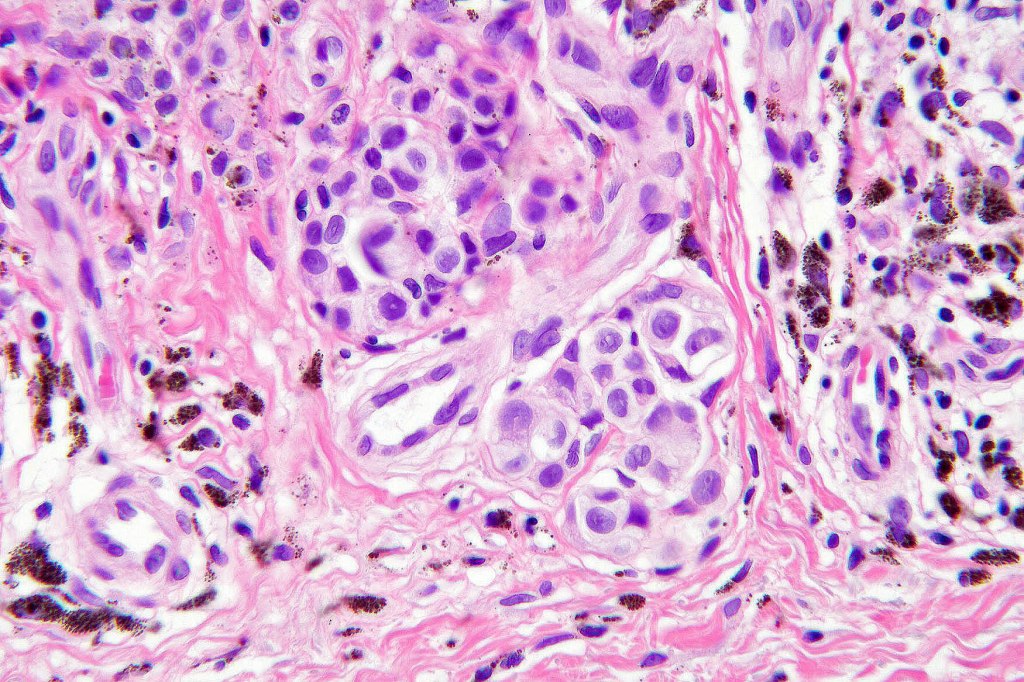

Histological features

•Enlarged cells with copious eosinophilic, foamy or clear cytoplasm (some authors include melanoma with clear cell change in the same category)

•Variable pigmentation

•Nuclei vesicular or hyperchromatic

•Pleomorphism is not generally marked and indeed can be very subtle

•Variable mitotic activity

•Thought to be a result of abnormal or degenerative melanosome change

•Cells stain with HMB45, SOX10, S100, Melanoma-A